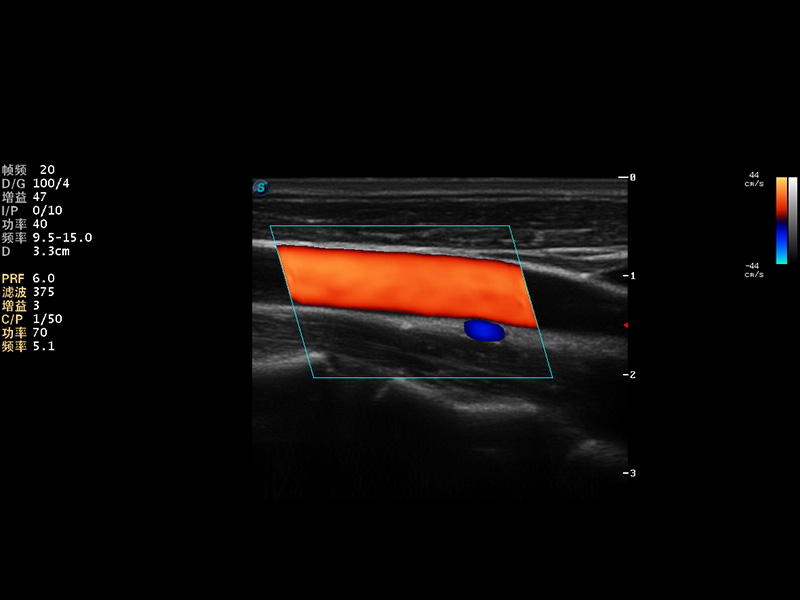

S9便携式彩色多普勒超声诊断仪是1xBET研发的高端便携彩超设备,外观设计新颖、产品性能卓越。S9在便携超声领域采用了突破传统的触摸屏交互设计,并以先进的软件硬件技术和设计理念,为您带来清晰的图像质量、稳定的工作性能和便捷的操作体验。

AutoC智能血流追踪